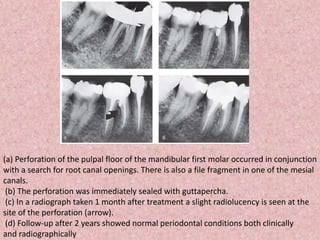

(a) Perforation of the pulpal floor of the mandibular first molar occurred in conjunction

with a search for root canal openings. There is also a file fragment in one of the mesial

canals.

(b) The perforation was immediately sealed with guttapercha.

(c) In a radiograph taken 1 month after treatment a slight radiolucency is seen at the

site of the perforation (arrow).

(d) Follow-up after 2 years showed normal periodontal conditions both clinically

and radiographically